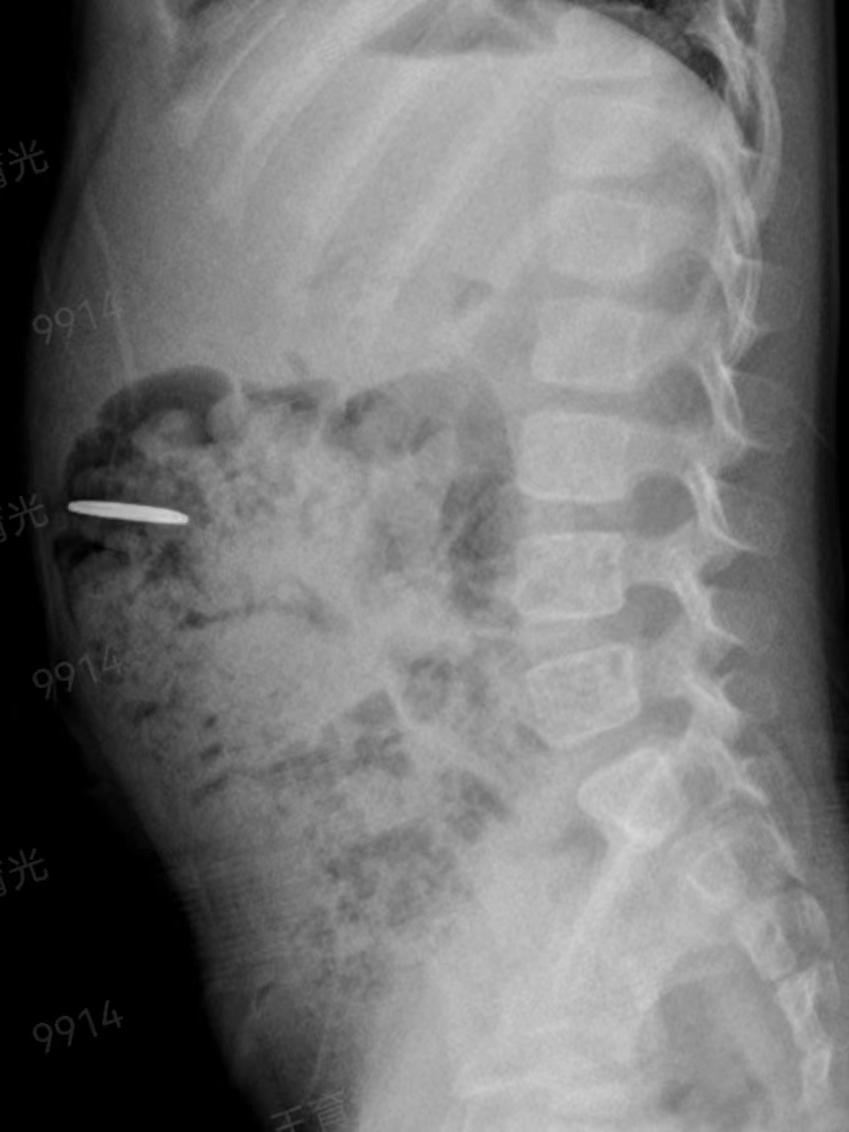

2023年11月27日晚上10時(shí),一名4歲女童誤吞一枚紐扣電池,女童的家屬發(fā)現後(hòu),心急如焚地將(jiāng)女童送至惠州六院急診醫學(xué)科,經(jīng)過(guò)腹部拍片檢查,醫務人員懷疑異物位于孩子的左上腹,不排除異物位于消化道(dào)的可能(néng)。

在無痛胃鏡的幫助下,手術團隊在小女孩的胃裡(lǐ)找到了那個硬币大小(直徑約1.5cm)的電池,卡在了幽門口,還(hái)好(hǎo)沒(méi)有進(jìn)入小腸。